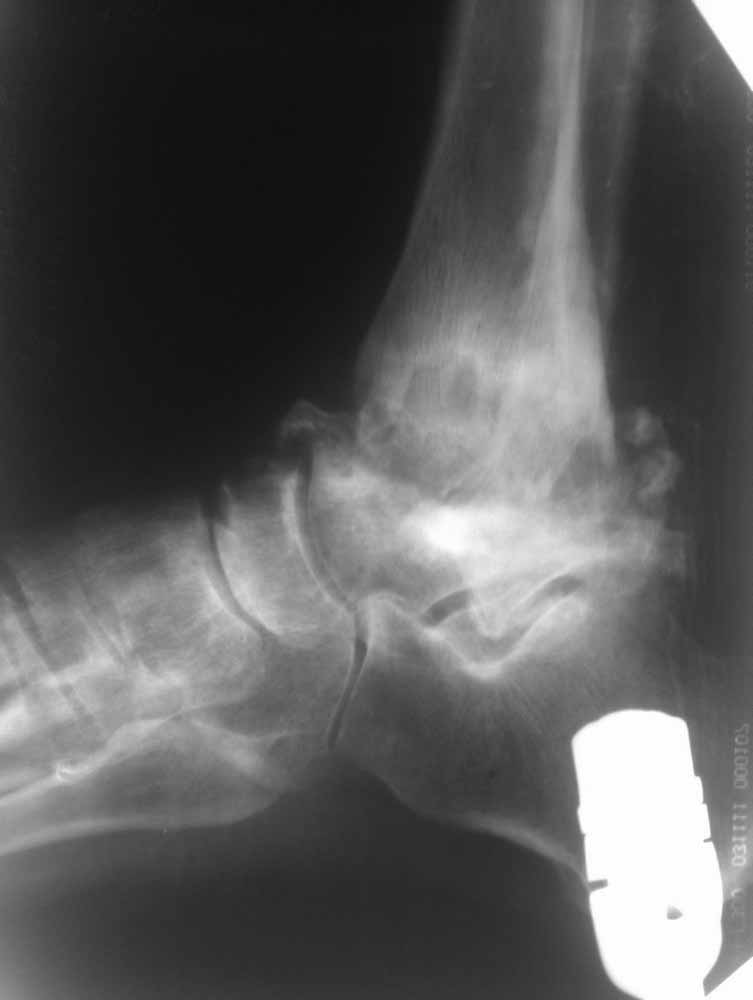

Да, вспомнил, была у нас такая пациентка. 20 с небольшим лет. СД 1 типа, тяжёлое течение, с 5 лет. Осложнения почти все, какие только могут быть - нефропатия, ХПН, ретинопатия, ангионевропатия, анемия 3 ст. и т.п. В анамнезе - кататравма. Оперировали в 2006, 2007 г., выполнялся панартродез на обеих стопах. В последующем всё плохо: неоднократные странные нагноения (после дренирования и 5 дней антибиотиков всё успокаивалось - до очередного обострения; при этом болевой синдром практически отсутствовал). Лечение сложное и дорогостоящее, вплоть до применения эритропоэтинов и т.п. Однако положение стоп сохранялось достаточно приличное, ходьба в ортезах. В 2009 г. появились жалобы на боли в других суставах. При обследовании (сцинтиграфии) были выявлены множественные очаги по всему организму, вплоть до деструкции головки плечевой кости (накопление РФП 200 - 1400%). Содержание свободных лёгких каппа-цепей 149,0 мкг/мл (норма 3,0 – 8,0 мкг/мл), лямбда-цепей 1,3 мкг/мл (норма 0,001 – 0,04 мкг/мл). Множественные повторные биопсии, трепанбиопсии и гистологии. Диф. диагностика с гематологическими заболеваниями, миеломной болезнью, амилоидозом (кстати, тогда я понял, что амилоидоз - это не совсем то, чему нас учили в своё время).

Головку плеча позже резецировали в другом стационаре. Больную видел этим летом, ходит всё также в ортезах (фиксаторы ГСС с боковыми шинками). Про остальное не спрашивайте.

Опять прошу прощения за качество фото, но принципиальные моменты мне кажется, что видны.

Из того, что я вместе с лучевыми диагностами разглядел - нельзя исключить остеомиелит (?) - есть краевая реакция, куча элементов, похожих на секвестры. Смущает полное отсутствие местной и системной реакции - к анализам не придраться.

Склоняемся к мысли, что все таки Charcot's Joint.

Прогрессивное разрушение скелета и характерную деформацию можно увидеть при нейропатической артропатии или Charcot arthropathy.